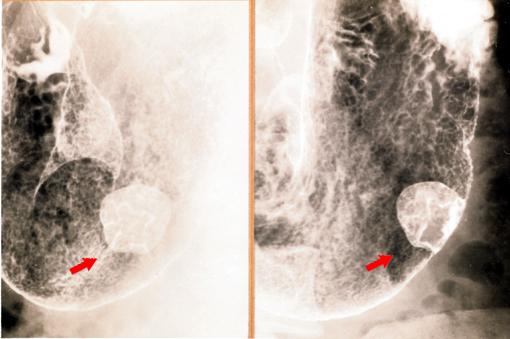

질환(병리주체)의 분류 악성 상피성종양/선암

부위(장기별) 위(부위)/체부

검사방법 X-P

종양의 육안분류 1형(종괴형)/

종양의 최대경(밀리미터) 25~29

종양의 심달도 m